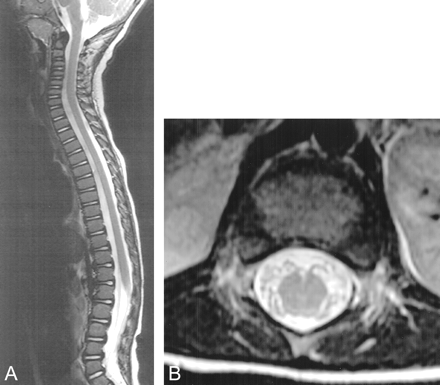

T2-weighted MR images (4000/105) display normal signal intensity within the substance of the spinal cord and lumbosacral nerve roots.

A, Sagittal view.

B, Axial view.